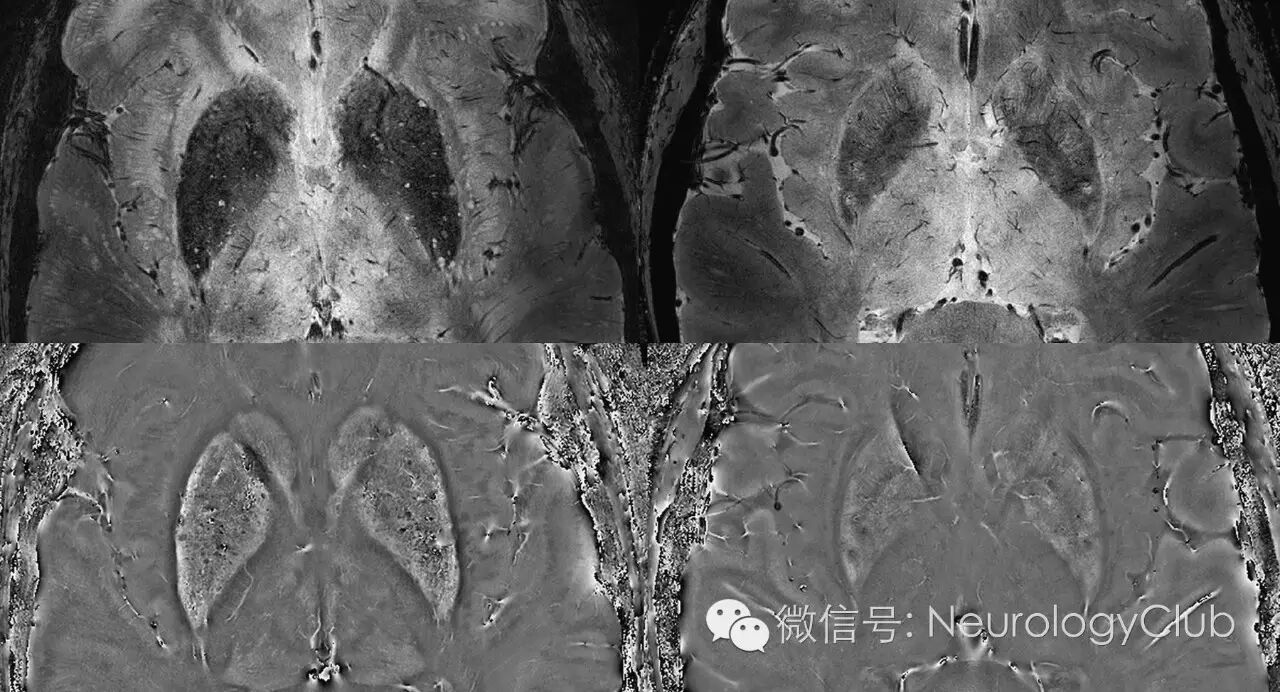

(图10:60岁CADASIL患者[左]和60岁正常人[右]。7T磁共振SWI上可见CADASIL患者壳核和尾状核弥漫铁沉积)